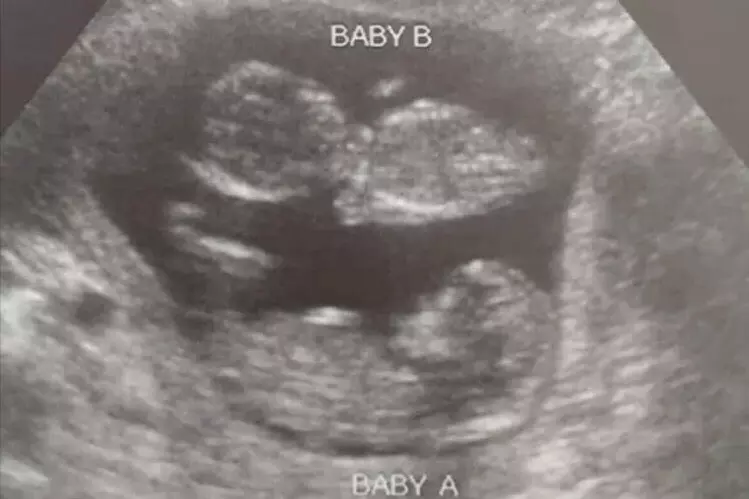

In a Facebook post made this week, Boles shared the following, along with a glowing picture of the unborn twins:

Problem #2: they didn’t tell her that she was having twins. Either their sonographer was incompetent, or they once again lied since they know that a woman who finds out that she’s having twins may have a harder time with the thought of aborting two babies instead of one.

Problem#3: and this really isn’t a problem - at least not for us. The abortion pill didn’t work. The patient is now very happy that it didn’t work. Why didn’t it work? Probably because the extra progesterone from the fact that there are two babies overcame the progesterone blockade that the abortion pill tries to create.

In evaluating his patient and the twins, Boles determined that extra progesterone via Abortion Pill Reversal wouldn’t be necessary this time around.

Boles says his most recent patient and her twins are in great health and concluded with stinging words on Planned Parenthood’s massive failure to provide actual help the trio in their hour of need.

Today, [the patient]’s more than 12 weeks and is very happy. Both babies, and mom as well, are going to be fine.